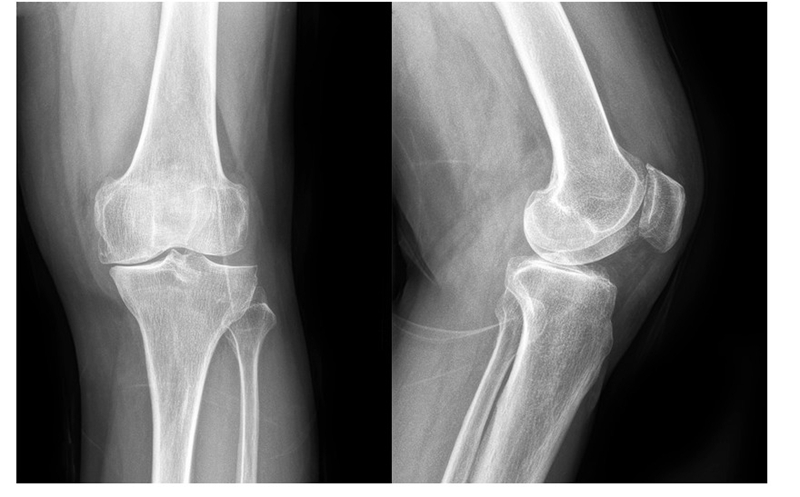

(1)70岁女性患者,以左膝关节疼痛5年、加重1年为主诉入院,入院查体左下肢内翻畸形11°,膝关节内侧间隙压痛阳性,外侧无压痛,髌骨研磨试验阴性,抽屉试验阴性,ROM 5°~120°,诊断左膝关节前内侧骨关节炎,行左膝关节内侧固定平台单髁置换术。术后给予预防感染、消肿止痛及抗凝治疗,术后24h康复师指导助行器辅助下床活动,术后1个月膝关节 HSS评分由63分升至85分,KSS评分由49分升至80分,内侧疼痛消失,患者恢复满意。手术前后影像学资料见图1~2。

图1术前 X线片示内侧间隙呈骨对骨改变

图2术后 X线片示假体位置良好,大小合适